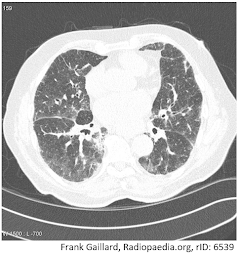

Diagnostica per immagini: l'accumulo di amiodarone aumenta l'attenuazione dei tessuti a causa del contenuto di iodio. Si tratta di un marker di esposizione e si osserva nel fegato, nella milza e nel polmone atelettasico.

La radiografia del torace tipica nella polmonite interstiziale mostra nuove opacità diffuse o localizzate, reticolari, consolidative o miste.

La TC ad alta risoluzione (HRCT) può chiarire il pattern radiografico e la distribuzione delle anomalie.

Si osservano opacità diffuse (di solito bilaterali) a vetro smerigliato e ispessimento dei setti, immagini a nido d’ape e bronchiectasie da trazione.